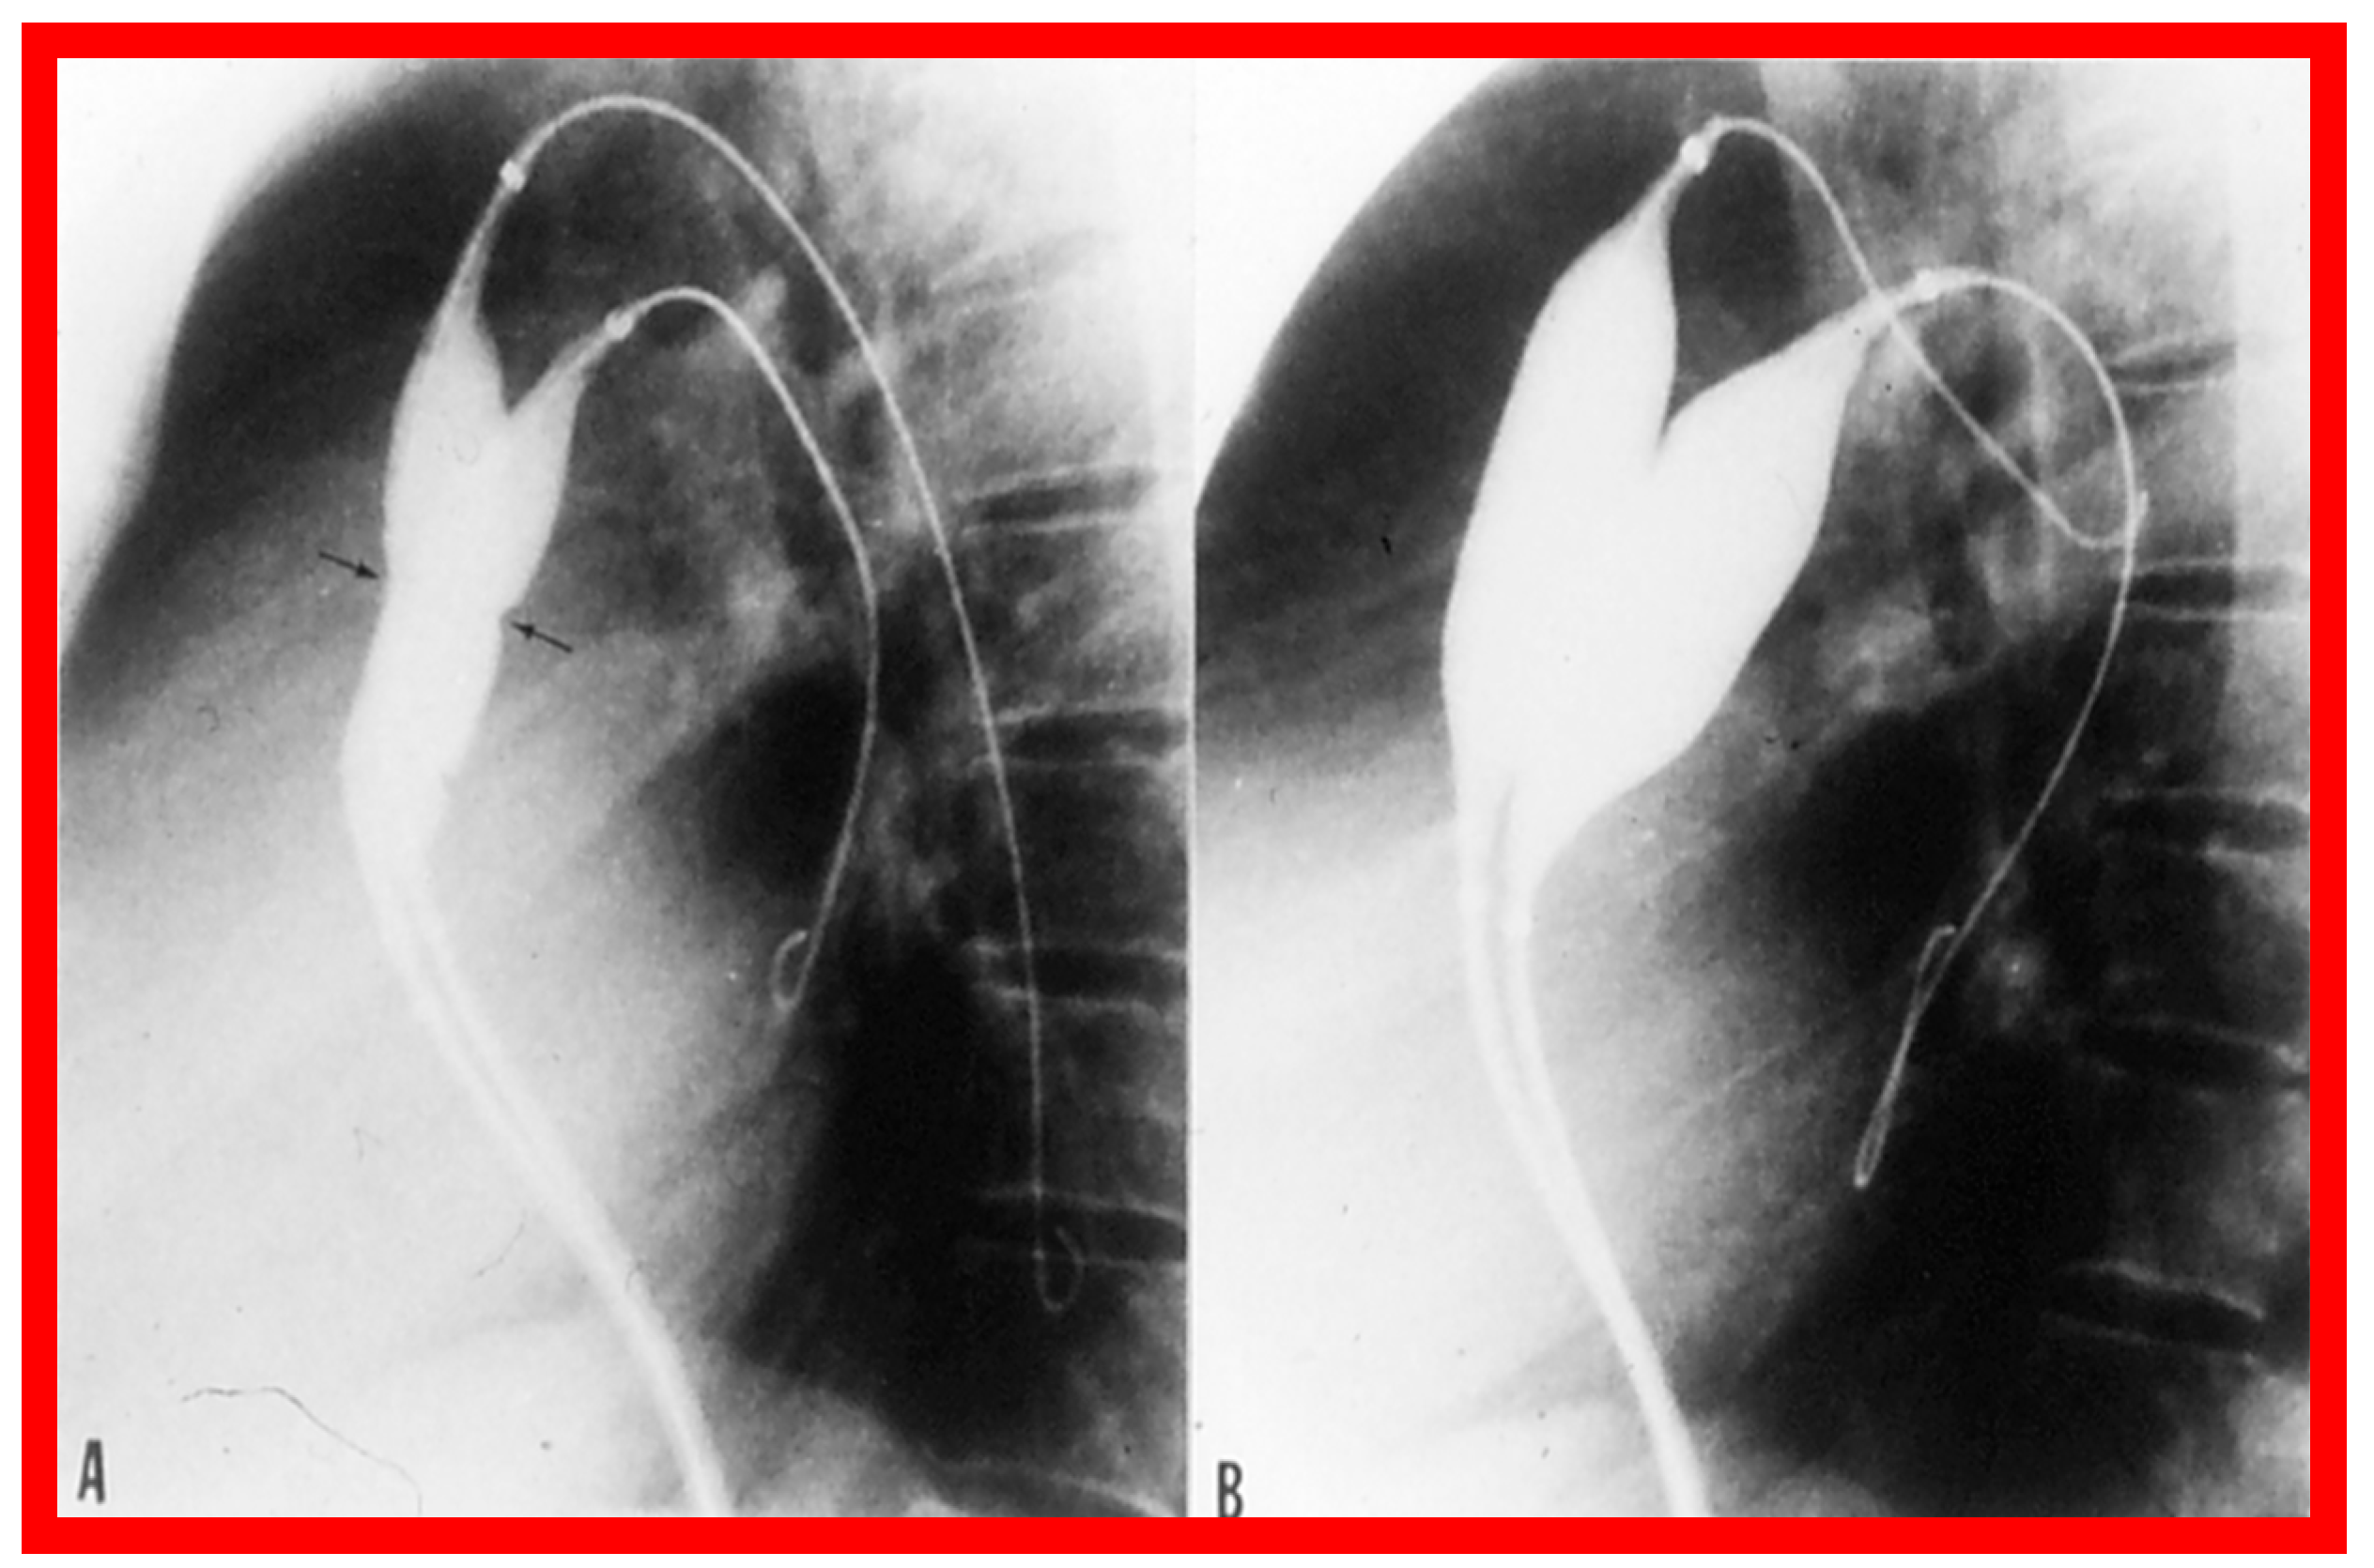

3.1. Pulmonary Stenosis

Pulmonary Stenosis in the Fetus